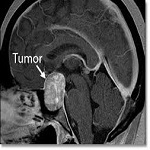

پزشکان و دندانپزشکان ← متخصص جراحی مغز و اعصاب